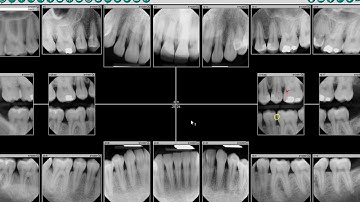

Launching DEXIS IS ScanFlow from DEXIS Imaging Suite Demo